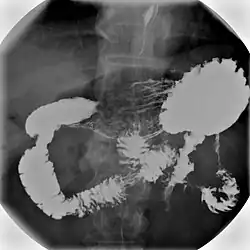

| Upper gastrointestinal series | |

Normal barium swallow fluoroscopic image, showing the ingested barium sulfate being induced down the oesophagus by peristalsis. | |